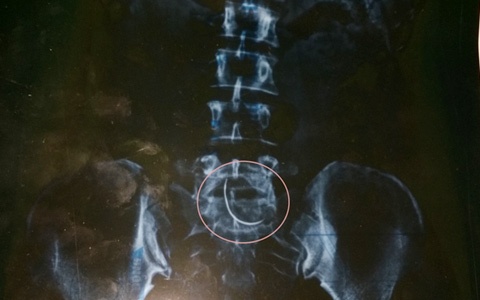

Sau khi chụp X-quang, vợ chồng chị Hòa hốt hoảng khi nhìn thấy chiếc kim khâu cong như lưỡi câu, dài khoảng 3-5 cm mà bác sĩ đã bỏ quên trong lần mổ sinh 9 năm trước.